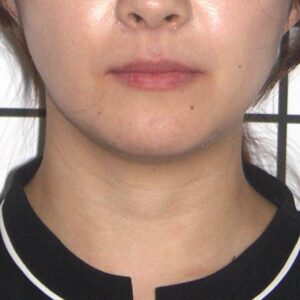

治療終了時

顔貌写真

口元を下げすぎずに治療終了できた